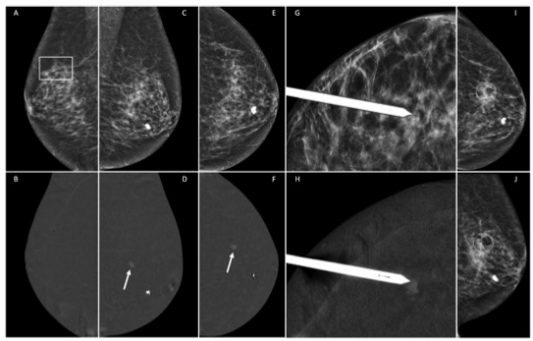

圖 一位無(wú)癥狀的77歲患者,有右側(cè)保乳手術(shù)史,在常規(guī)體外中心超聲檢查中發(fā)現(xiàn)可疑病灶后轉(zhuǎn)來進(jìn)行補(bǔ)充評(píng)估(圖像不詳)。右側(cè)乳腺的低能量CEM MLO視圖(A)顯示與手術(shù)后疤痕有關(guān)的結(jié)構(gòu)變形(矩形),重組圖像(B)上沒有顯示異常增強(qiáng)病變。左側(cè)乳腺重組圖像(D和F)顯示了一個(gè)偶然發(fā)現(xiàn)的7毫米增強(qiáng)腫塊(箭頭),在低能量圖像(分別為C和E)或超聲上未見顯示。進(jìn)行了左乳CEM引導(dǎo)下的活檢(G和H)。放射性標(biāo)志物的正確位置得到確認(rèn),通常的2個(gè)乳腺造影視圖(I和J)。病理報(bào)告:導(dǎo)管內(nèi)乳頭狀瘤